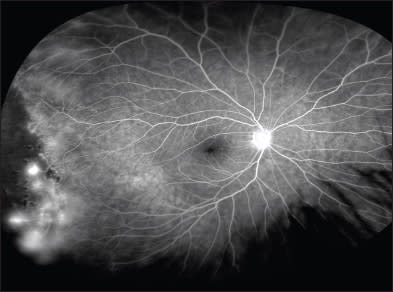

Figure 1. A widefield angiogram of a patient with Coats disease, demonstrating peripheral neovascularization and capillary dropout that could potentially be missed with traditional imaging (imaged with the Optos 200 Tx).

The majority of these diseases, such as diabetic retinopathy, hypertensive retinopathy, central retinal vein occlusion, and ocular ischemic syndrome, may affect the entire retina. Other diseases, however, including sickle cell retinopathy and Coats disease, may only present with changes in the retinal periphery, making imaging more difficult (Figure 1).